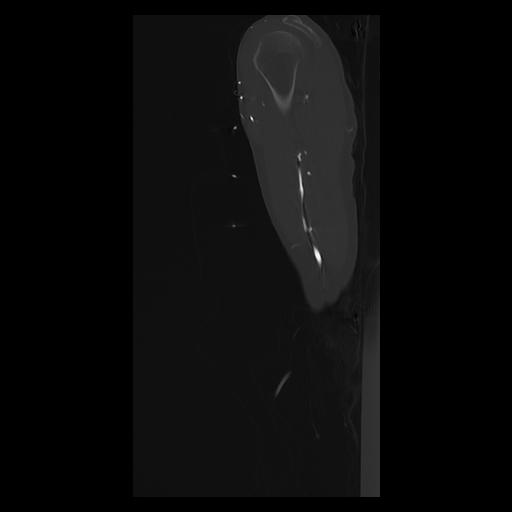

33 PULMON,CE,Sagittal,3.000,PULMON,Sagittal,